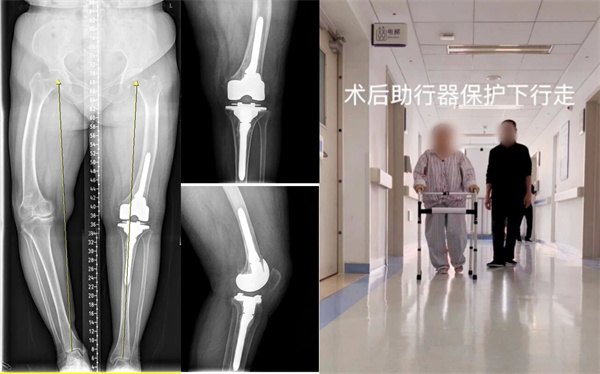

▲术前检查:双膝重度内翻变形,X线片双膝重度骨关节炎改变

入院完善相关检查后,运动医学与关节外科(骨二科)特聘专家邢更彦详细查看了患者情况。患者双膝呈重度内翻畸形,左侧为重,屈伸活动严重受限,膝内侧及髌股关节间隙明显狭窄,且左侧膝外侧副韧带存在松弛。邢更彦与患者及家属进行了深入沟通后表示,患者因重度膝内翻继发骨性关节炎,膝关节疼痛与活动受限已严重影响其日常生活。若采用传统膝关节周围截骨矫形,虽可恢复下肢负重力线,但患者年龄偏大且关节退变严重,无法确保有效缓解疼痛。对于如此严重的畸形合并侧副韧带松弛的情况,常规的初次膝关节置换手术亦不适用。经综合评估,团队最终为患者制定LCCK膝关节置换术手术方案。

经过充分的术前准备,在血库、麻醉科及第一手术区团队的通力协作下,手术顺利完成。术后,患者复杂重度膝关节畸形得到即刻矫正。次日患者即可在助行器辅助下进行负重行走锻炼。目前患者恢复良好,已顺利出院,并将择期进行右侧膝关节的手术治疗。

▲术后:X线见左下肢力线恢复正常,患者早期康复锻炼